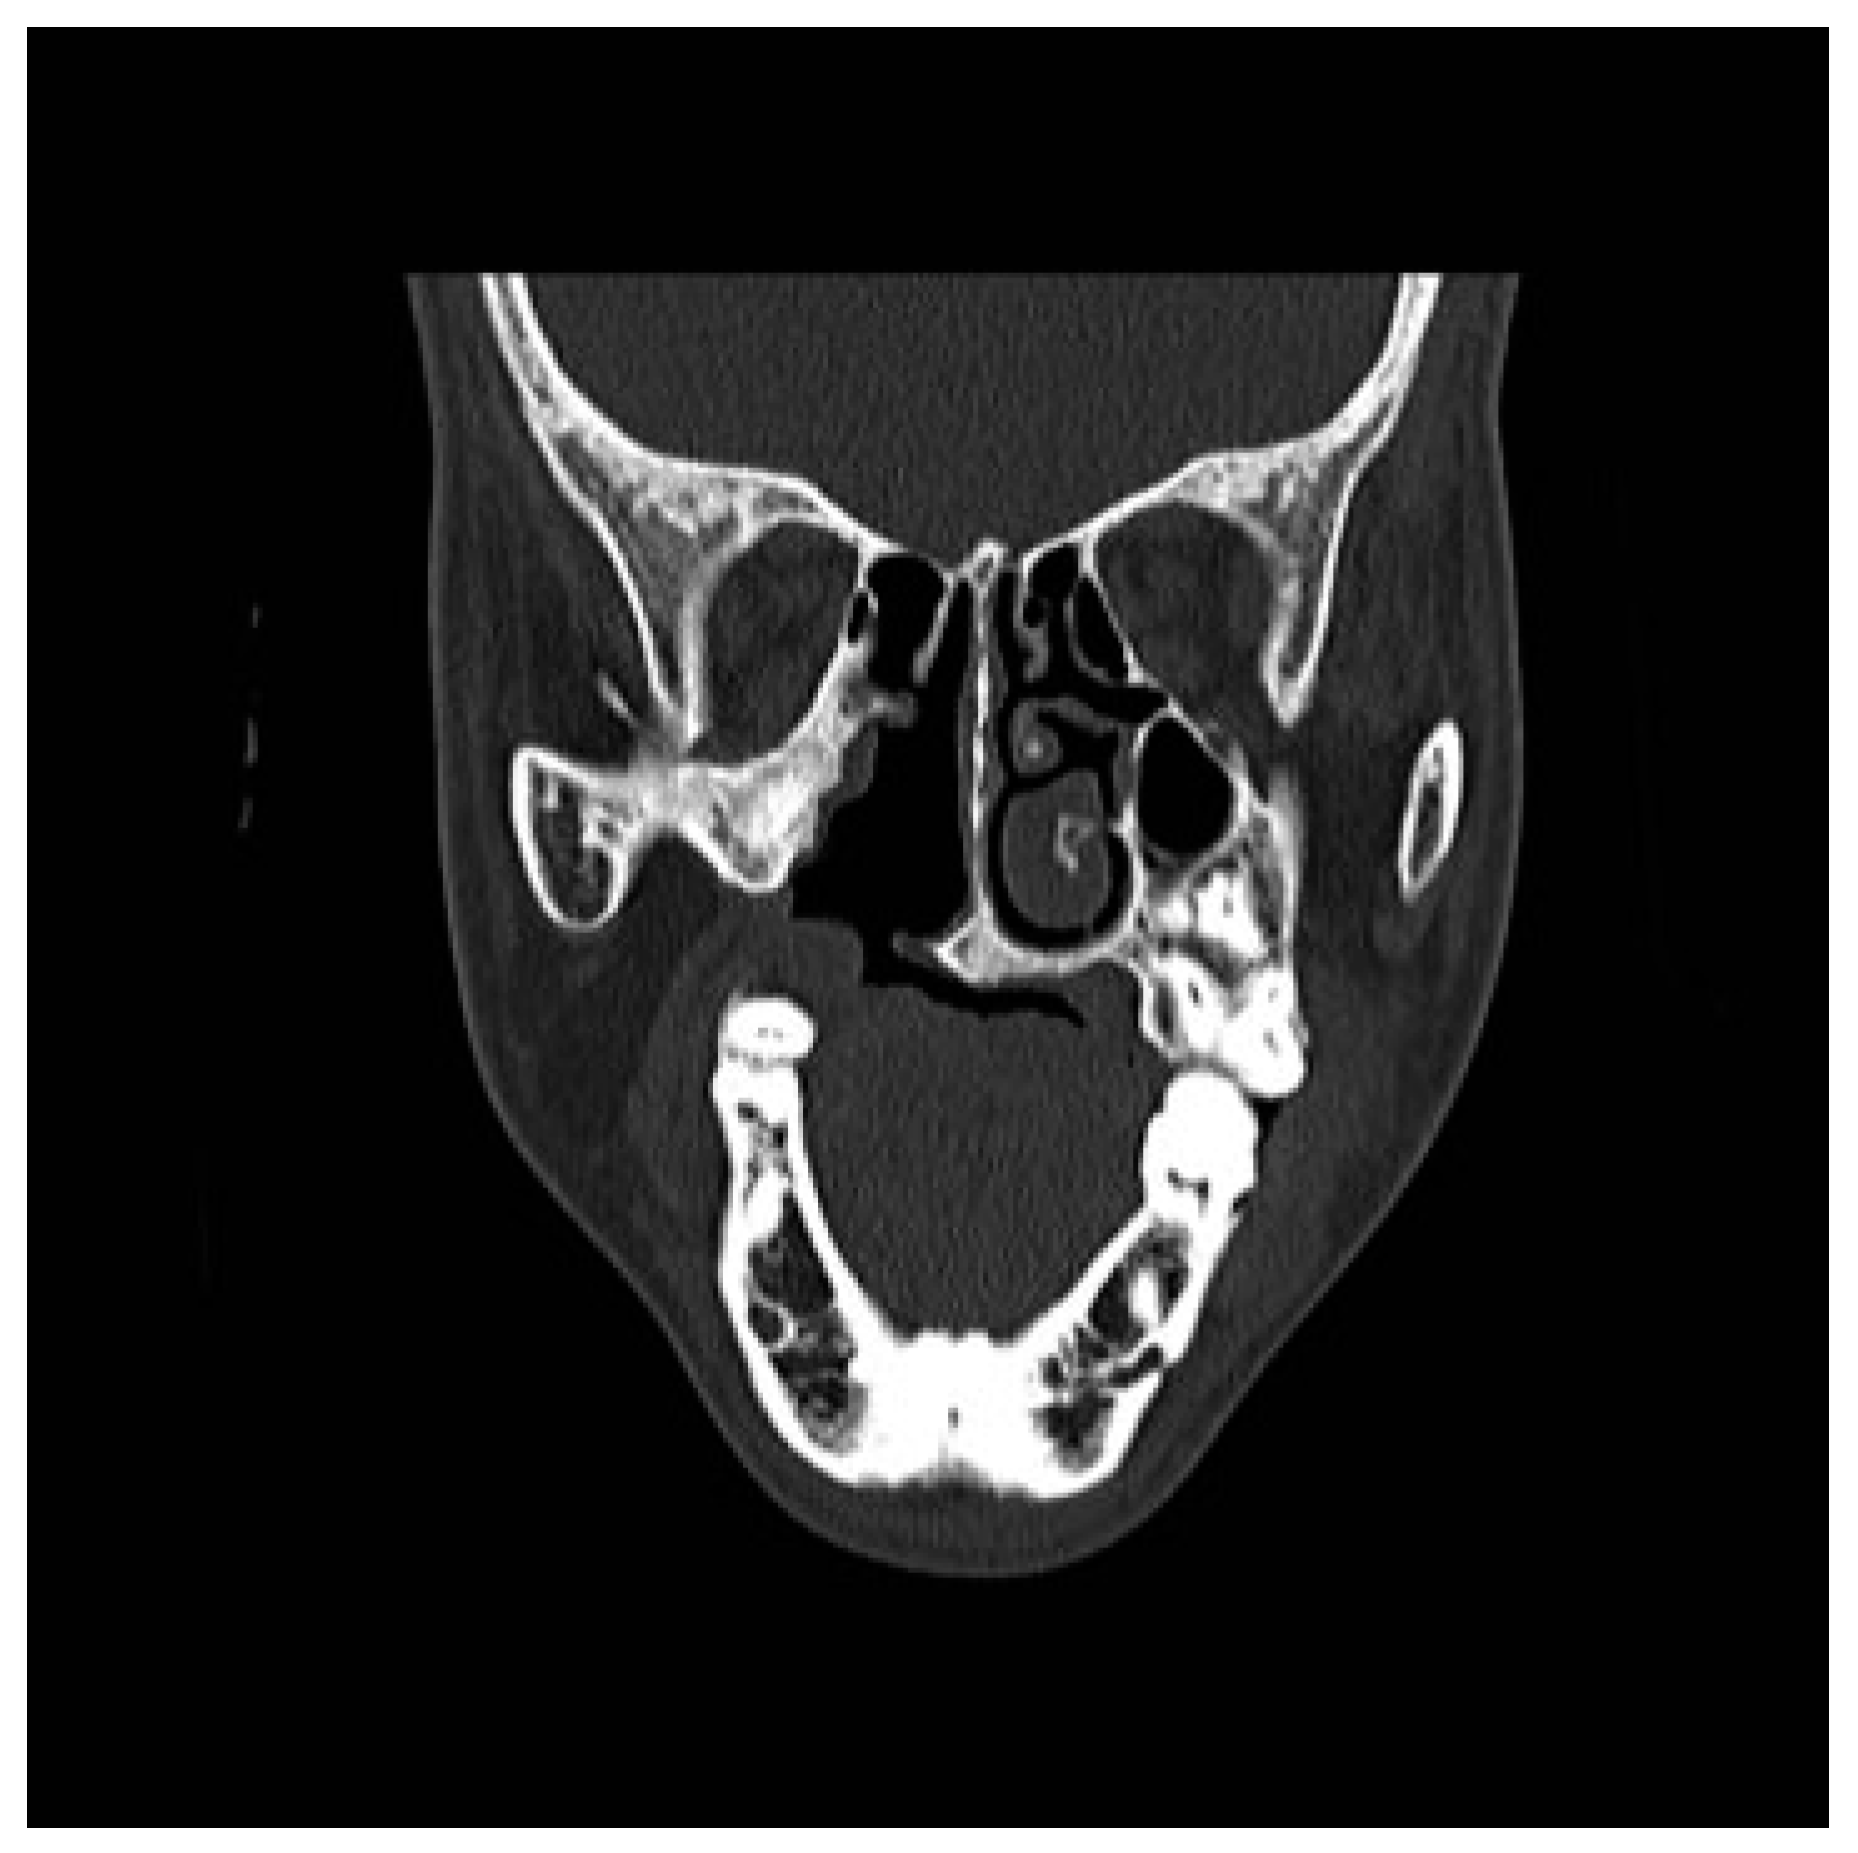

Figure 4. Preoperative CT scan. Coronal view: agenesis of the right turbinate and cleft palate.

Figure 2. Preoperative CT scan. Axial view: agenesis of the right turbinate and cleft palate.

A CT scan of the head with 3D reconstruction (Figure 1, Figure 2, Figure 3, Figure 4 and Figure 5) confirmed a maxillomandibular fusion associated with a cleft palate, agenesis of the right turbinate, and right hemifacial microsomia (Laster type 2b syngnathia). Both temporomandibular joints (TMJs) were normal and showed no bony ankylosis (fibrous ankylosis could not be excluded with the given data).